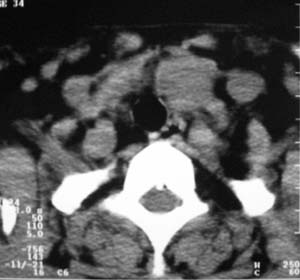

以下是引用zsl6918在2007-8-27 14:40:00的发言:[br]双侧甲状腺多发性低密度占位,边界清晰,密度欠均匀,尤以左侧明显,与周围组织分解清,考虑多发性腺瘤可能性大,不除外结节性甲状腺肿

以下是引用liaizhi在2007-8-27 15:20:00的发言:[br]双侧甲状腺散在多个囊性第密度影,左侧最大一个病灶与正常甲状腺分界尚可,气管受压稍右移。考虑甲状腺瘤的可能性大。